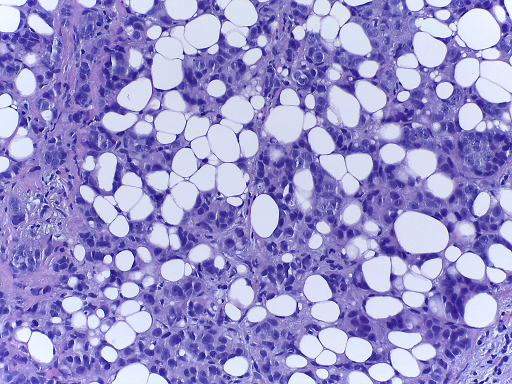

The microscopy dataset is composed of 400 training and 100 test images, with the four classes equally represented (see Fig. 2). All images were acquired in 2014, 2015 and 2017 using a Leica DM 2000 LED microscope and a Leica ICC50 HD camera and all patients are from the Porto and Castelo Branco regions (Portugal). Cases are from Ipatimup Diagnostics and come from three different hospitals (Hospital CUF Porto, Centro Hospitalar do Tâmega e Sousa and Centro Hospitalar Cova da Beira). The annotation was performed by two medical experts. Images where there was disagreement between the Normal and Benign classes were discarded. The remaining doubtful cases were confirmed via imunohistochemical analysis. The provided images are on RGB .tiff format and have a size of 2048×1536204815362048\times 1536 pixels and a pixel scale of 0.42 μ𝜇\mum ×\times 0.42 μ𝜇\mum. The labels of the images were provided in .csv format. Participants were provided with a partial patient-wise distribution of the images of the training set. The test data was collected from a completely different set of patients, ensuring a fairer evaluation of the methods. Note that the training set is an extension of the one used for developing the approach in [3].

Refer to caption

(a) Normal

(b) Benign

(c) In situ

(d) Invasive

Fig. 2: Examples of microscopy images from the BACH dataset.